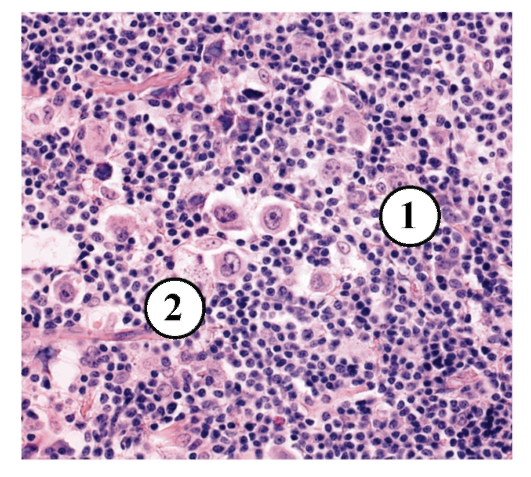

УЗИ лимфоузлов при лимфоме Ходжкина